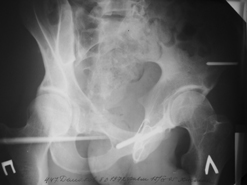

Диагноз : Сочетанная травма. ЗЧМТ. Перелом свода черепа. Ушиб головного мозга.Разрыв лонного и крестцово-подвздошного сочленений с нарушением целостности тазового кольца, с массивной забрюшинной гематомой и пропотеванием в брюшную полость. Перелом 10 ребра справа, осложненный гемопневмотораксом справа, правосторонней пневмонией на фоне ушиба правого легкого. Шок 3-4 ст. Больной поступил в отделение 07.03.2005г. в 16.00 в экстренном порядке через 30 минут после автодорожной травмы.Доставлен КСП. При поступлении состояние больного крайне тяжелое, явления травматического шока, А/Д-80/60 мм.рт. ст. ЧСС-120.В экстренном порядке поднят в операционную, интубирован, совместно с диагностическими мероприятиями лечение шока.При осмотре выявлены перелом 10 ребра справа, разрыв лонного и правого крестцово-подвздошного сочленений. Имеется линейный перелом теменной и височной костей слева с переходом на основание. Диагностическая лапароскопия 07.03.2005г. в 16.30-массивная забрюшинная гематома малого таза.Оставлена контрольная, дренажная трубка.Учитывая кровь в моче произведена цистография - данных за разрыв мочевого пузыря не найдено. Больной переведен в реанимационное отделение.За 08.03.2005г. из брюшной полости выделилось до 1500,0 мл, крови, часть крови реинфузирована. 08.03. в 06.30 наложен торокоцентез справа,удалено 100,0 мл. крови и 200,0 мл. воздуха .. Учитывая продолжающеееся кровотечение в брюшную полость из перелома костей таза, для исключения возможного разрыва внутренних органов 09.03.2005г. произведена Видеолапароскопия., на которой повреждения органов брюшной полости не выявлено.Одновременно произведен шов лонного сочленения проволокой и винтами, с одномоментным наложением стержневого аппарата на кости таза, с целью уменьшения кровотечения из разрывов тазовых сочленений, дренирование гематом. В последующем состояние больного оставалось тяжелым. 10.03.наложена нижняя трахеостома.Далее неоднократно производилась лечебно-диагностическая ФБС.С 10.03 выявлена правосторонняя плевропневмония. КТ головного мозга от 10.03-субарахноидальноекровоизлияние.Срединные структуры не смещены. КТ-контроль от 15.03-открытая моновентрикулярная гидроцефалия4 желудочка. Полисинусит. Постепенно состояние больного медленно прогрессировало к улучшению.С 24.03 переведен на самостоятельное дыхание, а 09.03 переведен в травматологическое отделение.Аппарат стержневой снят из-за перелома стержня (раскрутил больной самостоятельно).После госпитализации в наше отделение проведено дополнительное обследование Рентгекнография, КТ.Хотелось бы услышать Ваше мнение о дальнейшей тактике.-- С уважением, Leonid

Углядел билатеральное повреждение таза. Имеется вертикальная нестабильность со стороны перелома боковой массы крестца, ротационная с контрлатеральной стороны - чрезподвздошный разрыв кп сочленения. Разрыв лона, запирательные отверстия вроде целы.

DS. на сегодняшний день: Вертикальная двусторонняя нестабильная деформация таза, неправильно срастающийся перелом боковой массы крестца слева, срастающийся перелом крыла правой подвздошной кости, застарелый частичный разрыв правого кп сочленения, застарелый разрыв лонного сочленения.

План жизни - оперативное лечение. ЧКО таза (кольцевая опора), последовательная фиксация задних отделов с низведением перелома крестца, синтез лона пластинами, илиосакральное блокирование.

Следует заметить, что подобное привинчивание проволокой лонных костей редко приносит удовлетворение и то только при ротационно-нестабильных повреждениях от бовового сжатия без "ручки корзины". Разрушение заднего комплекса делает неэффективным любую фиксацию передних отделов. Надо обезательно хватать задние отделы.